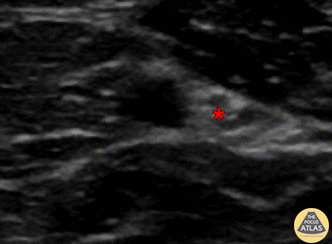

In-plane ulnar nerve block, with needle seen entering from screen right (ulnar aspect), with anesthetic sequentially deposited deep, lateral, then superficial to ulnar nerve (*). The ulnar artery can be seen pulsating to the left of (radially to) the ulnar nerve. Denver Health Ultrasound Fellowship Archive